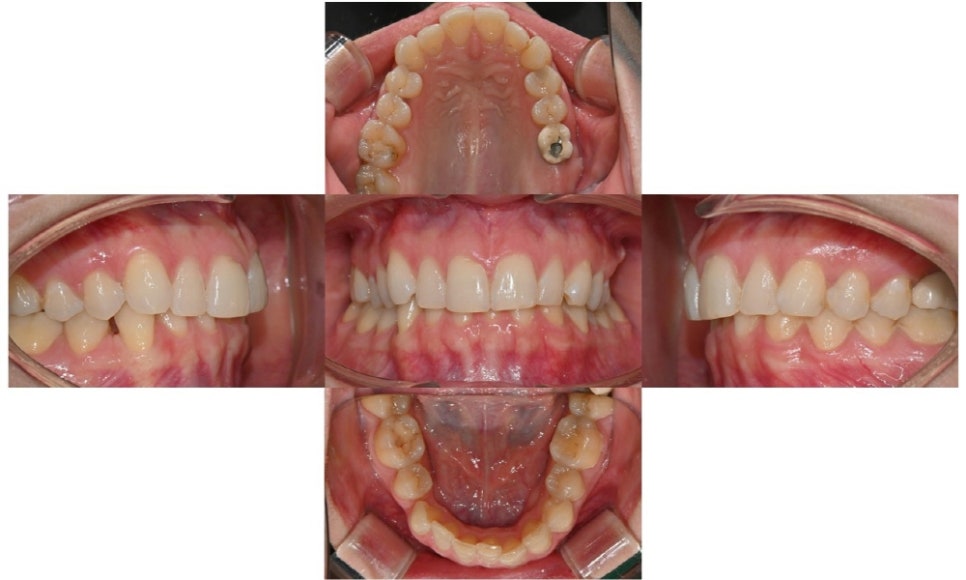

- 구강내 사진

위 앞니 두 개의 중 왼쪽 앞니의 사이즈가 오른쪽보다 살짝 커서 이 부분이 가장 불만이라고 하셨으며, 위아래 앞니에 약간의 치아 배열이 틀어져 있었습니다. 과거 하악 발치 교정으로 인해 하악 제1소구치가 발치되어 있었고 우측에는 공간이 약간 남아있었습니다. 또한 과개교합으로 인하여 아래 앞니는 거의 보이지 않는 상태였습니다. 왼쪽 제1대구치에는 임플란트가 식립된 상태였고, 제2대구치는 상실된 상태였습니다.